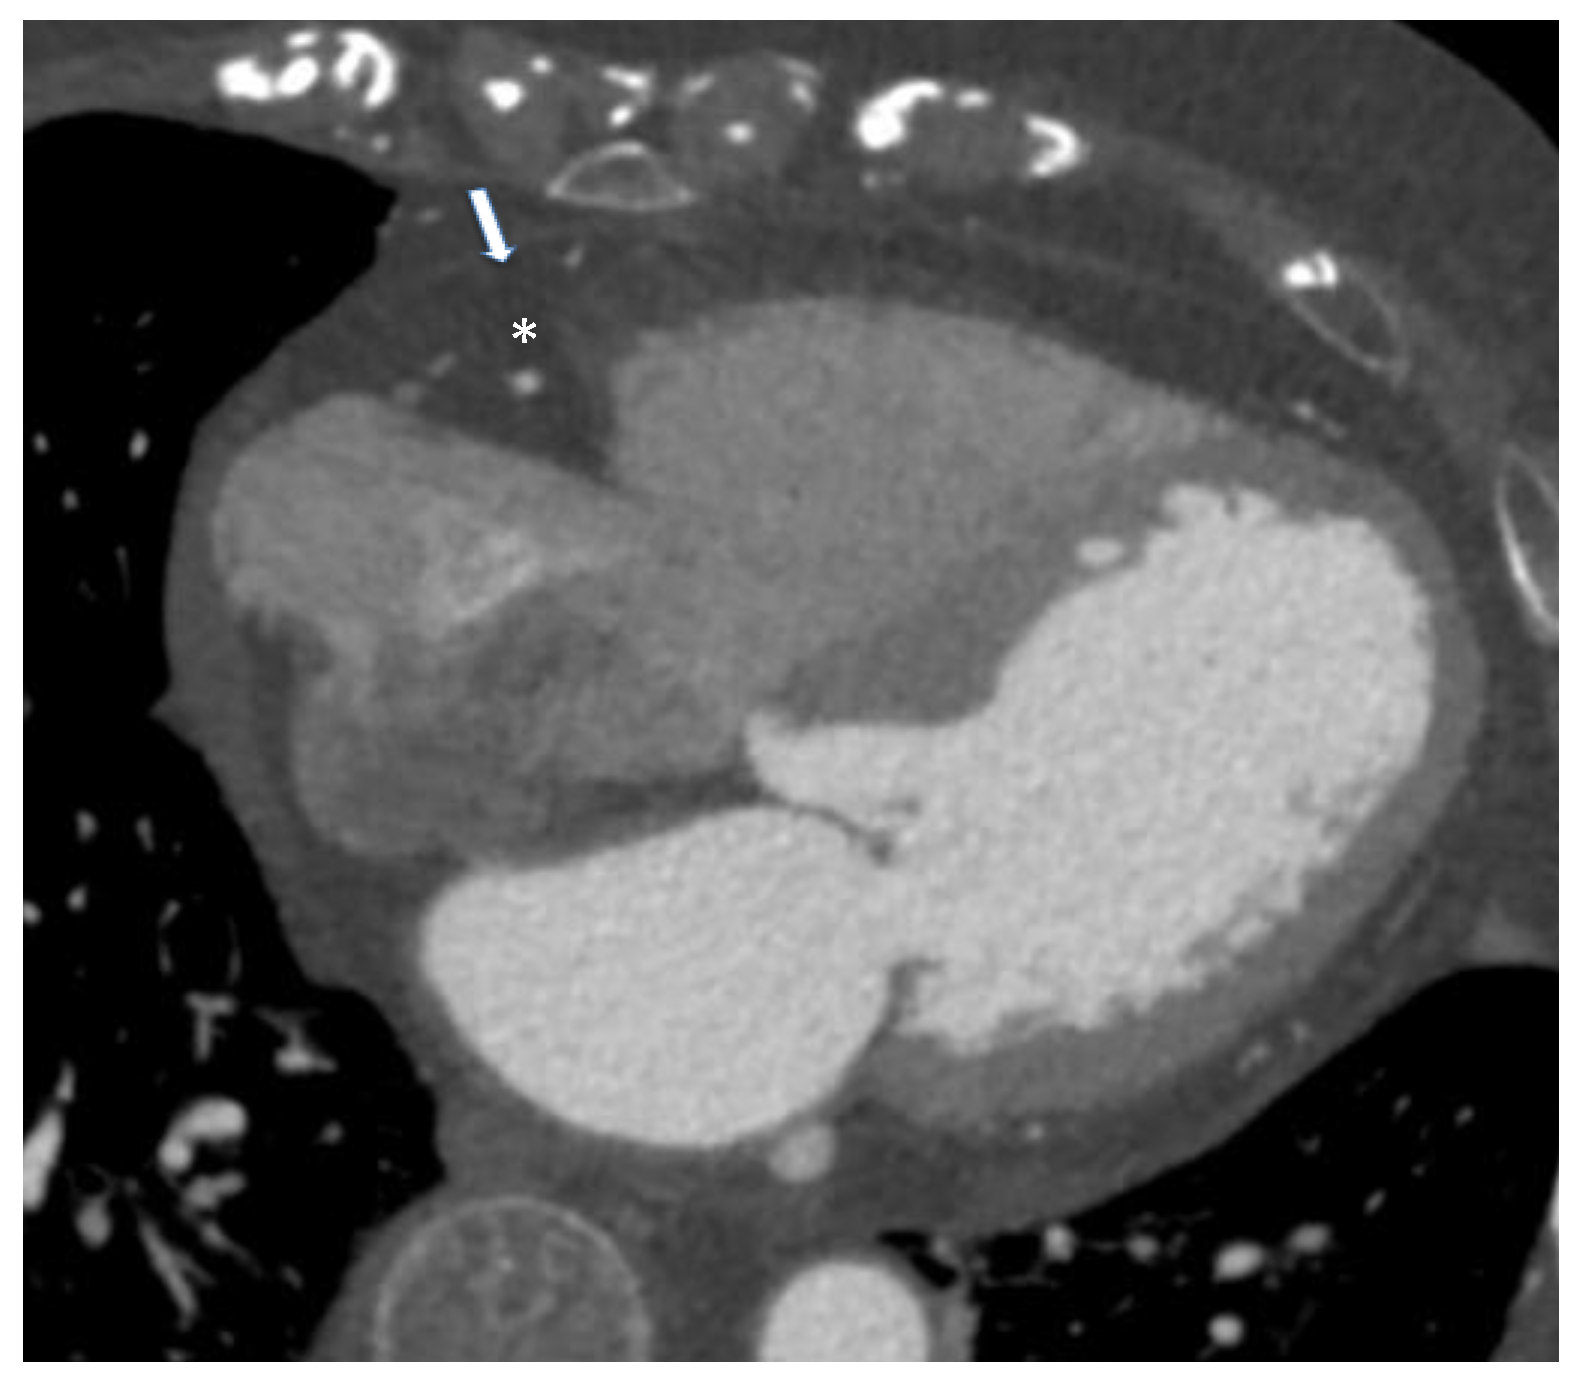

- Monti, C.B.; Codari, M.; De Cecco, C.N.; Secchi, F.; Sardanelli, F.; Stillman, A.E. Novel imaging biomarkers: Epicardial adipose tissue evaluation. Br. J. Radiol. 2020, 93, 20190770. [Google Scholar] [CrossRef] [PubMed]